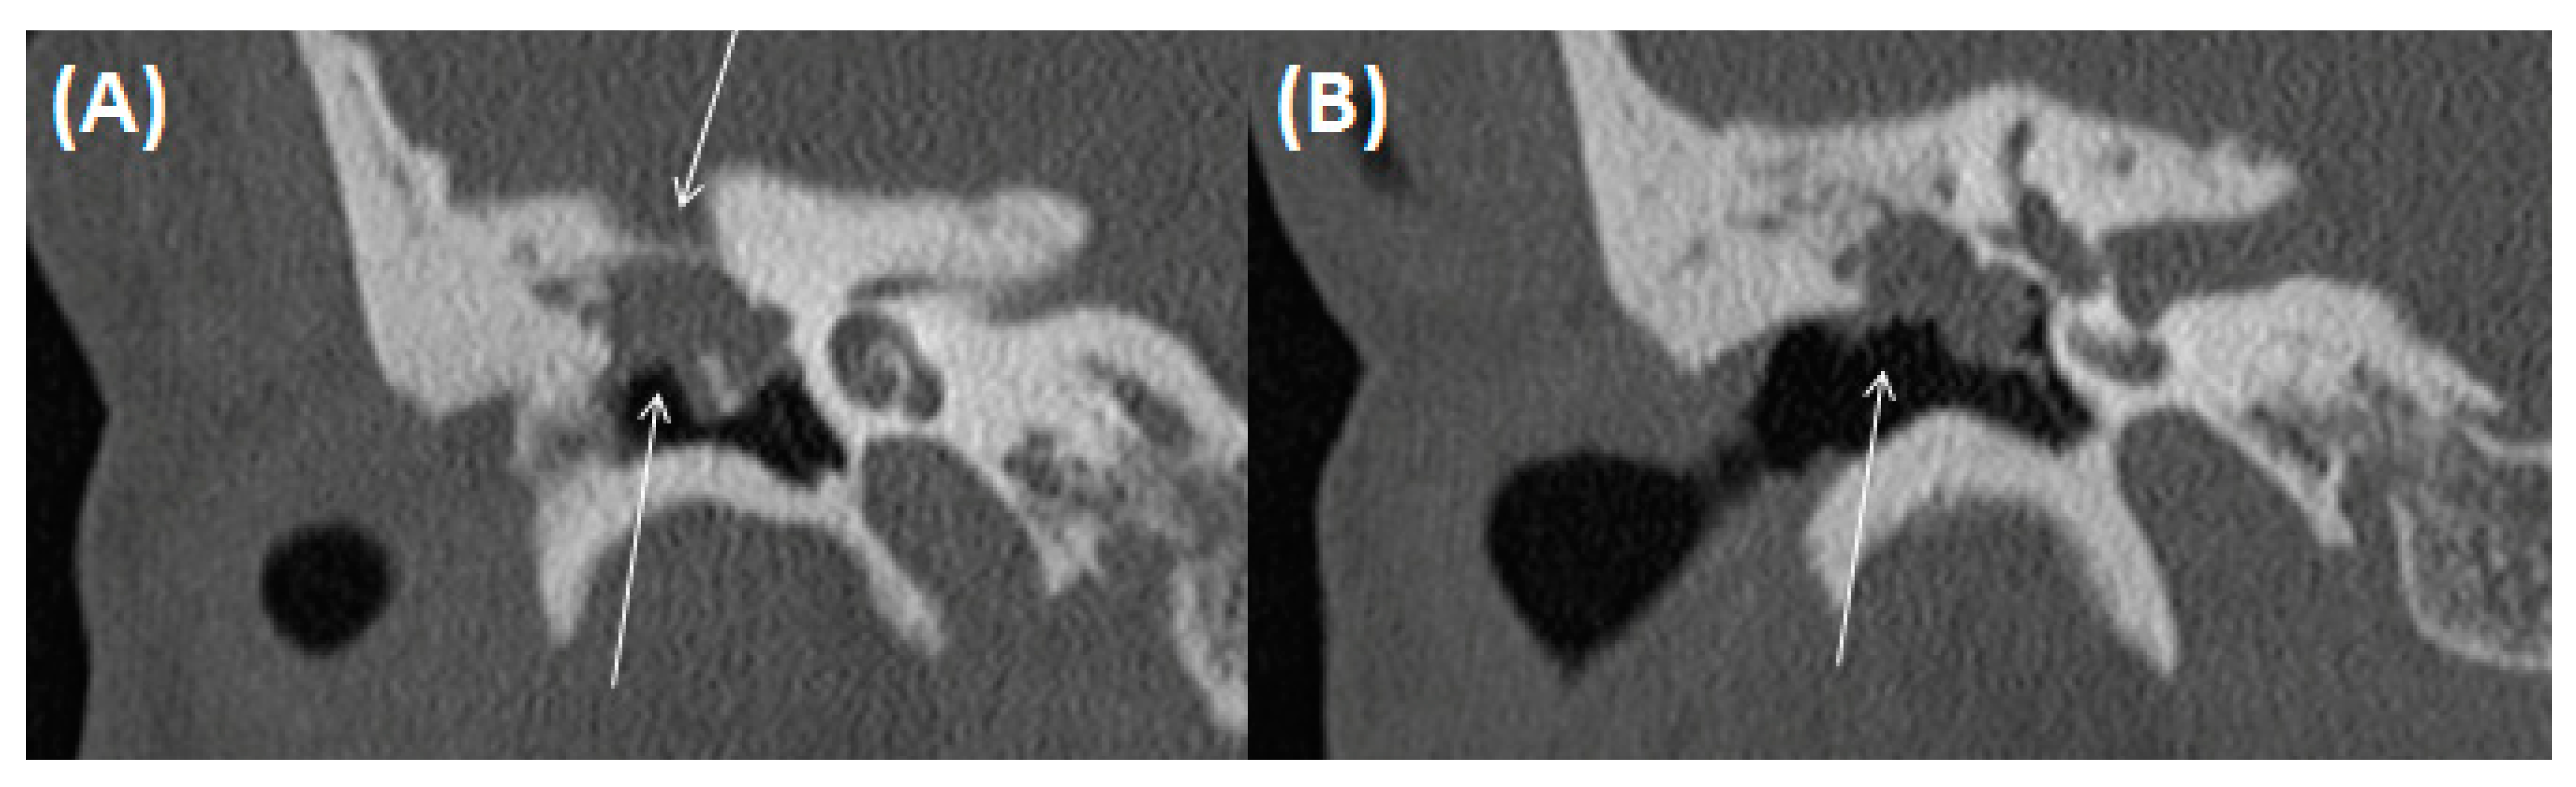

3.2.3. Tympanosclerosis

3.2.4. Cholesteatoma of the Middle Ear

3.2.5. Cholesterol Granuloma